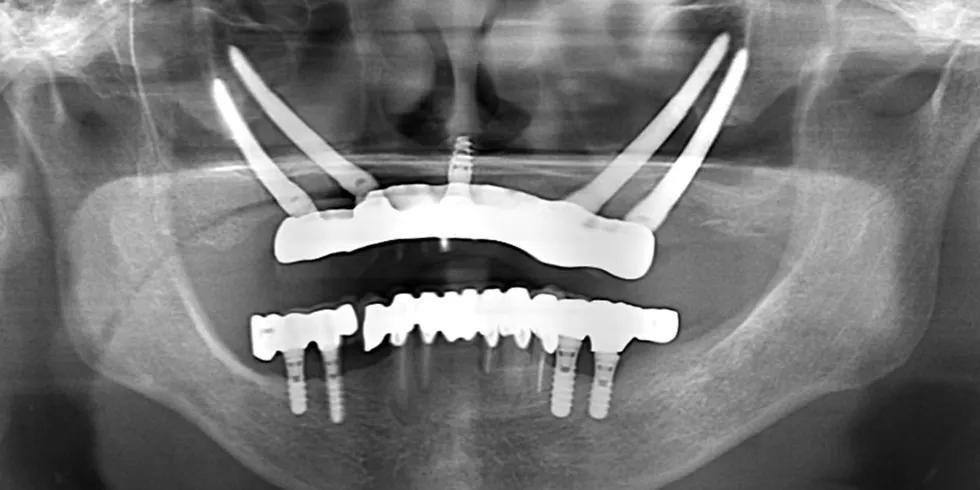

インプラント症例4(ザイゴマ)

クワッドザイゴマを用いた上顎インプラント治療(全身麻酔あり)

手術前パノラマX線写真

手術前パノラマX線写真

治療名

クワッドザイゴマを用いた上顎インプラント治療(全身麻酔あり)

患者情報

70代女性

執刀医

Dr.今井

治療内容

骨が全くなかった為、ザイゴマインプラントを4本埋入しました。

費用

¥4,268,400(税込)

リスク

- 治療が受けられる歯科医院が限られている(ザイゴマインプラントは、頬骨に入れるインプラントですので、治療の難易度が高く、行っている歯科医院がごくわずかに限られています。)

- 治療費が高額(ザイゴマインプラントでは、通常のインプラントとは違う特殊なインプラントを必要とします。また、特殊な技術を必要とするため、治療費が通常のインプラントより高額になります。)

- 長時間の手術が必要になる(頬骨に手術を行うため、通常の顎に行うインプラントと比較して、手術時間も長く必要になります。)

歯科医師からの説明

一般に静脈内鎮静法は2時間を越えると薬剤蓄積や局所麻酔薬の効果や姿勢、尿意などの問題が起きやすくなります。

その点、全身麻酔は全身麻酔器などの設備や詳細な術前検査、人工呼吸用の管を鼻より通したりといった処置が必要となりますが

術中のストレスや痛みは皆無となります。